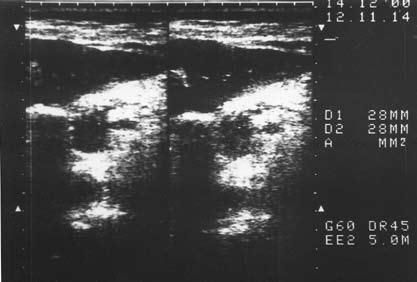

К сожалению, и специальные методы не во всех случаях позволяют решить рассматриваемую дифференциально-диагностическую задачу. Так, исследование крови больного на карбогидратный антиген (СА19-9) и раковый эмбриональный антиген (РЭА) дает отчетливо положительный ответ лишь при достаточно больших размерах опухоли, часто в неоперабельных случаях. Исследование ПЖ с помощью ультразвука или на компьютерном томографе дает увеличение размеров железы, в особенности ее головки, и при ХП, и при раке, а также выявляет очаговые образования тех или иных размеров, причем для рака более характерно одиночное гипоэхогенное образование, а при ХП поджелудочная железа чаще изменена диффузно, она гиперэхогенна (более плотная), содержит множественные кальцификаты (см. рис. 137–139), хотя точно дифференцировать характер очагов удается далеко не во всех случаях. Трудности дифференциальной диагностики ХП и рака ПЖ по данным УЗИ и КТ иллюстрируют рисунки 142–145.

Рис. 143. Ультразвуковое исследование. Хронический псевдотуморозный панкреатит. На снимке видна гипоэхогенная бугристая "опухоль" головки ПЖ 3x3,5 см (1)